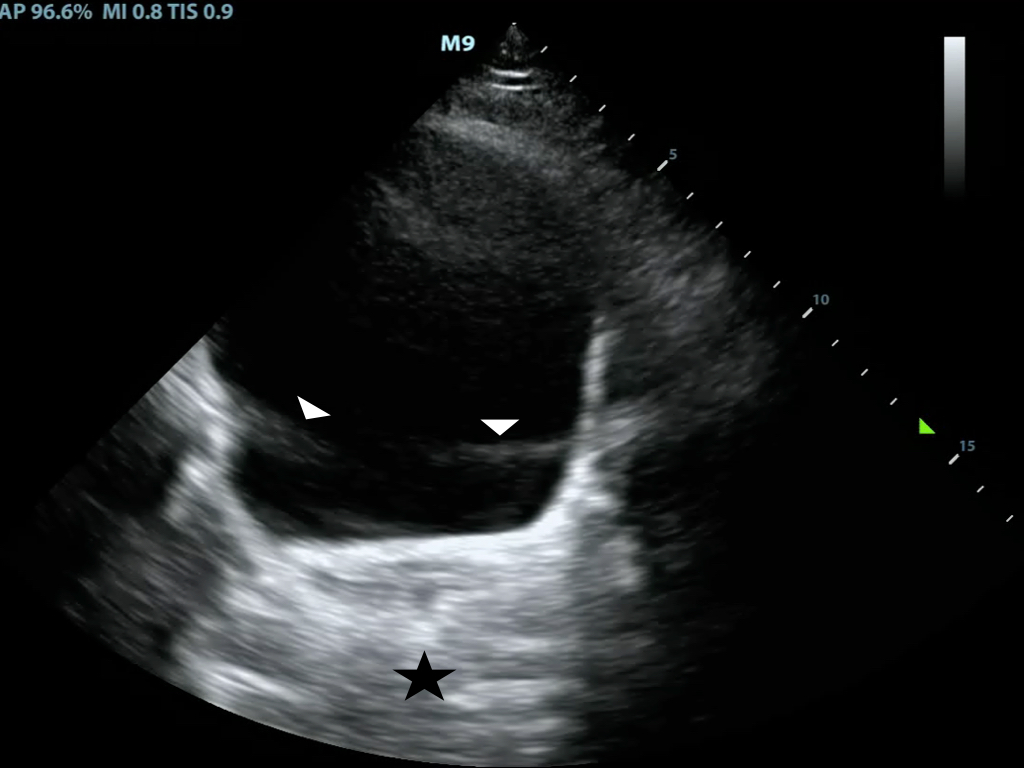

- Shadowing is caused by partial or total reflection or absorption of the sound energy

- A much weaker signal returns from behind a strong reflector (air) or sound-absorbing structure (gallstone, kidney stone, bone) (Figure 7)

- Figure 7. Shadowing from gallstones and edge artifact at lateral wall of gallbladder

- Edge Shadowing Artifact is a thin acoustic shadow behind lateral edges of cystic structures

- Sound waves encountering a cystic wall or a curved surface at a tangential angle are refracted with few echoes returning to the transducer (Figure 7)